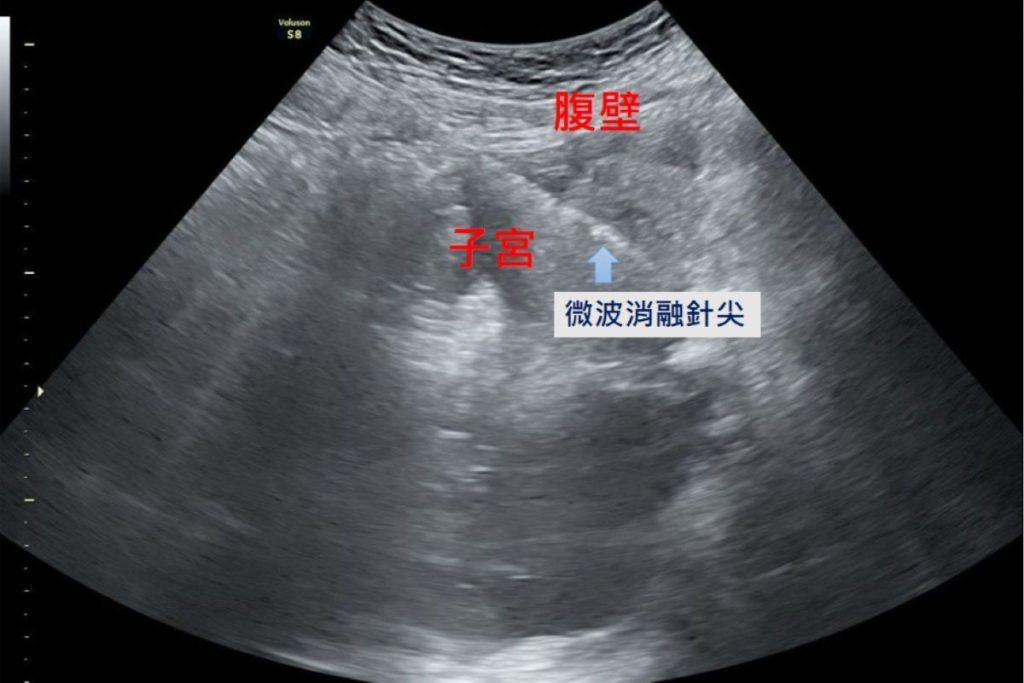

隨著醫療科技的進步,微波消融成為近年來的治療新選擇。醫師在腹腔鏡及婦科超音波的導引下,將消融針精準進入病灶,釋放高能量微波破壞異常內膜腺體組織,使其失去活性而逐漸縮小壞死,達到止痛與減少經血的治療目的。